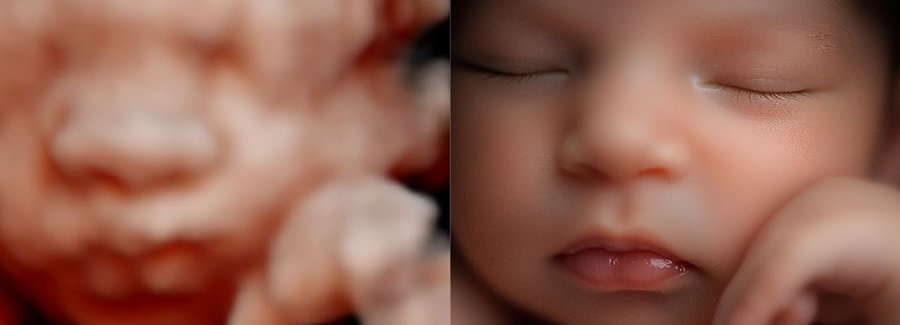

The best time to see your baby’s face in 5D/HD is between weeks 25 and 30 of your pregnancy.

Often referred to as 5D, HD or FRV (fetal realistic view), 5D/HD is the newest development in pregnancy imaging. It captures and combines high definition volume data to create automated images with amazing color and clarity so you can see your baby as though you were looking from inside the womb.